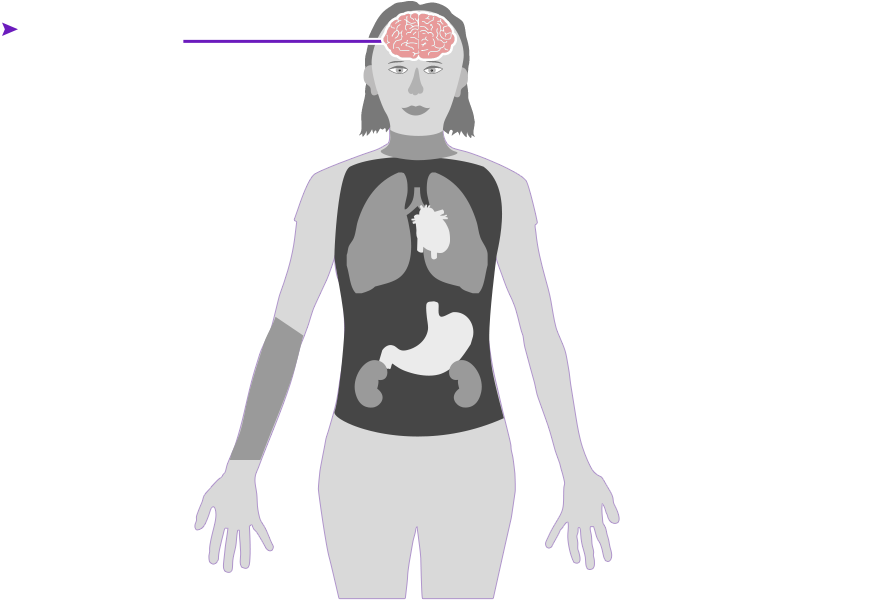

Check out how mercury can affect the human body. Click on the different parts of the body to see what can happen when people are poisoned by mercury. How serious these health effects are may vary depending on how much mercury gets into your body — and how long you breathe it in.

Health effect caused by breathing in high levels of mercury vapors (fumes) over a short period of time

Health effect caused by breathing in high levels of mercury vapors (fumes) over a short period of time  Health effect caused by breathing in lower levels of mercury vapors over a long period of time